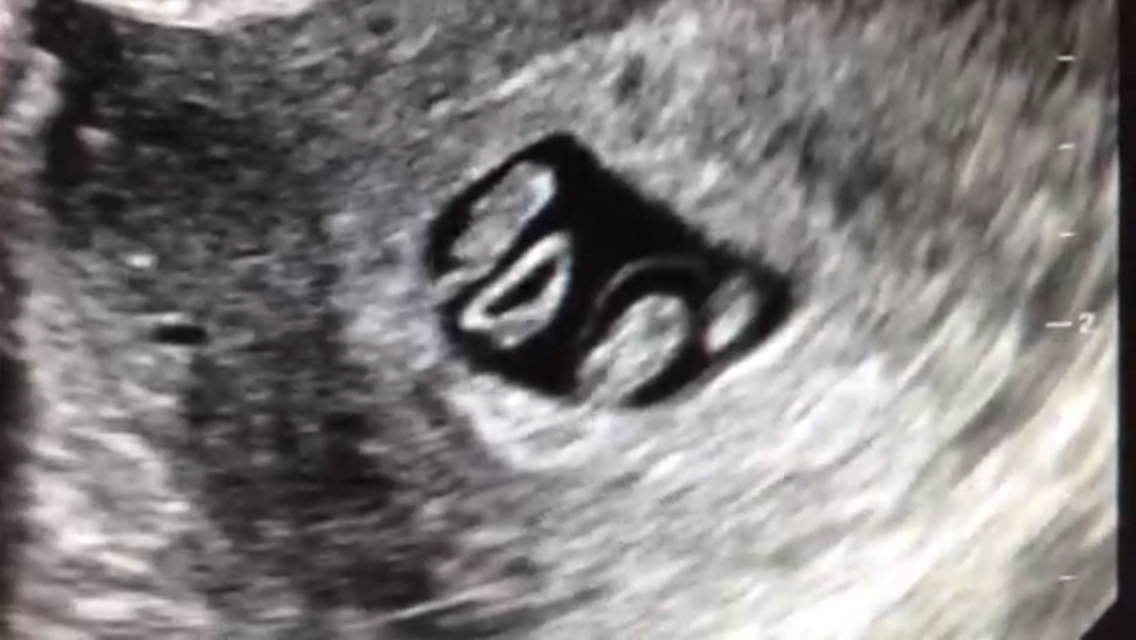

FTM! So excited to see how much my little gummy bear has grown in two weeks! 1st pic is at 6w5d, HR 147, and just a little blob with a flickering heart. 2nd & 3rd pics are at 8w5d, HR 176, and looked so much like a tiny baby with bitty arms and legs. Doc says baby is healthy and quite a dancer, it was moving and waiving all over the place. What a blessed moment to see!